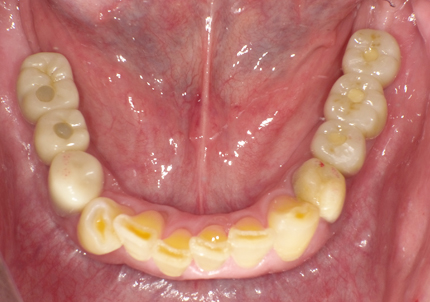

1.初診時口腔内写真(2014年6月)